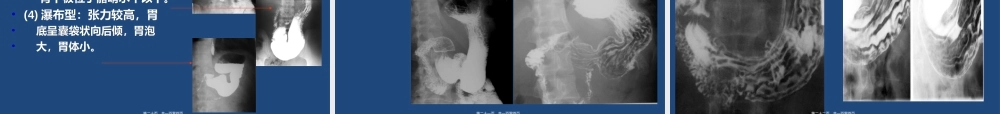

上消化道造影检查第一页,共一百零四页。胃肠钡餐检查显示胃肠道的大体解剖形态有其优势,并可进行动态和功能观察,和内镜检查有很好的互补作用。高质量的上消化道钡剂检查和内镜相比,两者诊断的正确性非常接近。第二页,共一百零四页。上消化道造影适应症•11、先天性食管异常、先天性食管异常•22、食管异物、食管异物•33、吞咽困难或胸骨后不适感、吞咽困难或胸骨后不适感•44、疑心消化道肿瘤或确定消化道肿瘤部位、大小、形态、疑心消化道肿瘤或确定消化道肿瘤部位、大小、形态和范围。和范围。•55、门脉系统疾病或结缔组织疾病,观察有无食管静脉、门脉系统疾病或结缔组织疾病,观察有无食管静脉曲张或食管功能性改变。曲张或食管功能性改变。•66、了解有无纵膈肿瘤、心血管疾病、肺及胸膜病变、了解有无纵膈肿瘤、心血管疾病、肺及胸膜病变等疾病对食管、胃或十二指肠外压性和牵拉性改变等疾病对食管、胃或十二指肠外压性和牵拉性改变•77、上消化道肿瘤术后、上消化道肿瘤术后第三页,共一百零四页。上消化道造影检查禁忌症•11、上消化道出血活动期、上消化道出血活动期•22、腐蚀性食管炎急性期、腐蚀性食管炎急性期•33、、肠穿孔、低位小肠梗阻。肠穿孔、低位小肠梗阻。•44、一般情况极差,难以耐受检查者。、一般情况极差,难以耐受检查者。第四页,共一百零四页。硫酸钡造影的观察内容粘膜皱壁:走行方向、光滑度、连续性、宽度粘膜皱壁:走行方向、光滑度、连续性、宽度管腔:大小、轮廓、钡剂通畅度管腔:大小、轮廓、钡剂通畅度管壁:柔软性、收缩性管壁:柔软性、收缩性消化道的位置和活动度:分布位置、活动度消化道的位置和活动度:分布位置、活动度第五页,共一百零四页。硫酸钡造影前的病员准备检查日晨禁饮、禁食检查日晨禁饮、禁食如有幽门梗阻者应抽尽潴留液如有幽门梗阻者应抽尽潴留液钡灌肠检查,如需显示消化道粘膜,应吃少钡灌肠检查,如需显示消化道粘膜,应吃少渣饮食渣饮食1-21-2天,检查前晚口服泻剂、去除粪天,检查前晚口服泻剂、去除粪便,检查当日禁饮、禁食。必须严格执行!便,检查当日禁饮、禁食。必须严格执行!碘剂碘剂第六页,共一百零四页。钡剂的浓度180~250%W/V钡剂的量200ml胃肠道双比照检查用钡第七页,共一百零四页。病人在检查时先给予适量产气粉,使胃腔有适当的充胀,然后给予吞服钡剂并在透视下观察,并按一定的顺序进行观察和摄片。第八页,共一百零四页。常用的上消...